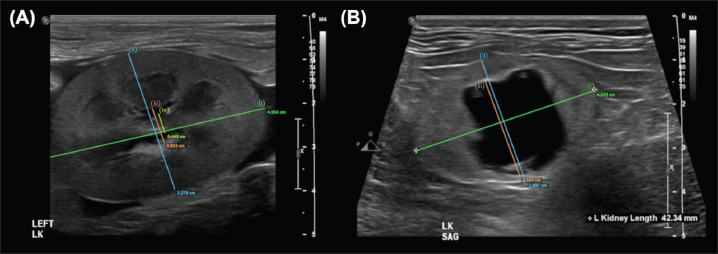

Discussion

The greatest overall interobserver agreement was achieved by standardized measurements between the renal crest and proximal ureter in the dorsal (DCU) and transverse (TCU) planes (Figs. 2a and b), even though anatomical definitions of the ‟ureteropelvic junction” are lacking in the veterinary and human medical literature (Stringer and Yassaie, 2013). One review of literature examining normal human kidneys concluded that a discrete pyeloureteral junction might not be present, and that in most individuals there might be a gradual zone of transition between the pelvis and ureter. Similar studies are lacking in the veterinary literature. While the unipyramidal morphology of the feline kidney differs from that of the multipyramidal kidney in humans, the embryological development is comparable (Hyttel et al., 2010), and a similar ‟pyeloureteral region” might also be expected in these patients. The ambiguous definition of the pyeloureteral junction might have less impact on interobserver agreement in specific images, however, if the angle of insonation is not perfectly centered and parallel to the long-axis of the proximal ureter. In this scenario, the medial cortical parenchyma or adjacent hilar fat may appear as a discrete, faint echo at the medial aspect of the collecting system due to slice thickness artifact. These echoes could provide a ‟pseudo-margin” for calliper placement, which could increase interobserver agreement. We attempted to minimize the effects of these phenomena by providing clear instructions and allowing the observers to reject images that they considered inappropriate for interpretation in a clinical setting. Our results, therefore, likely reflect the standard that would be encountered during retrospective measurement of still images in clinical practice. Furthermore, if a standardized measurement can be performed reliably and found to correlate with or differentiate between clinical entities, it has value as a diagnostic tool. In these circumstances, whether the region measured represents the precise anatomical boundaries of the renal pelvis is not as important as the reliability with which the measurement can be repeated between observers.

Fig. 2. Examples of the DCU (A) and TCU (B) measurement methods, which had the highest interobserver agreement of all methods examined in this study.

The standardized measurements with ‟excellent” interobserver agreement were between the renal crest and pyeloureteral junction in the transverse (TCU) and dorsal (DCU) planes. The TCU measurement approximated that which appears most commonly in the veterinary literature and is the most often utilized method at the authors’ institution; it is possible that this increased familiarity and experience with performing this measurement contributed to the high degree of interobserver agreement. Our finding that the TCU measurement produced excellent interobserver agreement validates comparisons between these previous studies and justifies its continued use for the sake of maintaining comparability between studies and clinical examinations. The similarity between the interobserver agreements for TCU and DCU measurements is also not unexpected; though performed in different planes, both methods direct observers to measure the distance between the same two anatomical locations.